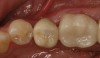

Fig 19. Lingual view of the screw-retained implant crown after placement of the composite “patch.”

Figure 19

Fig 20. Facial view of screw-retained implant crown.

Figure 20

Fig 21. Occlusal view of the screw-retained implant crown.

Figure 21